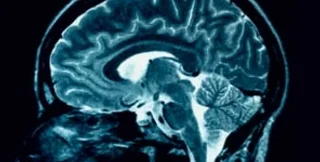

По результатам исследования профессора Хорхины Монтемайор Флорес, первая стадия любви сопровождается особыми химическими реакциями в мозге. При этом человек не может думать ни о чем, кроме объекта своих чувств. По словам ученых, подобное состояние свойственно тем, кто страдает обсессивным маниакальным синдромом (ОМС), при котором могут возникать навязчивые идеи – к примеру, о микробах или о злых собаках. Как и у больного ОМС, у влюбленного снижен уровень гормона серотонина, регулирующего настроение: стало быть, высока подверженность депрессиям. Коллеги мексиканцев, итальянские ученые, подсчитали, что у студентов, признающих себя влюбленными, содержание серотонина на 40% ниже, чем у остальных. Потому-то природа и ограничила такие чувства сроком в 4 года, после которых наступает более спокойный период любви – привязанность.